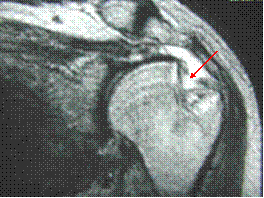

Hill-Sachs lesion

Impaction fracture from anterior dislocation.

Anterior glenoid impacts on superior posterior

humeral head